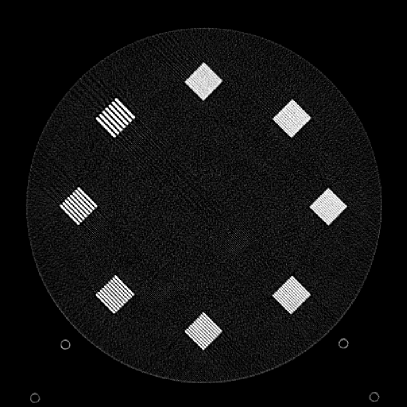

Figure 10: Clinical Standard hybrid IR vs JENG performance, with a display window center of 650 HU and a window width of 1500 HU. The spatial frequencies for bar patterns from top going clock-wise are 1.2, 1.0, 0.9, 0.8, 0.7, 0.6, 0.5, 0.4 mm-1. (a) The clinical Standard hybrid IR at L1 denoising strength using a soft tissue high contrast kernel. Note that significant aliasing streaking artifacts are present near the bar patterns. (b) JENG at a comparable L1 noise level but with much clearer bar pattern and fewer artifacts than the clinical standard hybrid IR. (c) The clinical standard hybrid IR at a stronger denoising strength of L3. (d) JENG at a comparable L3 noise level.

The first experiment we performed was a visual comparison of in-plane spatial resolution between JENG and the clinical standard hybrid IR. We used the ACR phantom module 4 for this evaluation, which has 8 resolution bars of various spatial frequencies from 0.4 mm-1 to 1.2 mm-1. To obtain a fair comparison, we matched the image noise variance in the uniform regions of JENG and the clinical standard hybrid IR and studied their in-plane spatial resolution and undersampling streaking artifacts. In addition, we performed two sets of experiments. The first set of experiments matched their image noise variance at the L1 denoising strength of the clinical standard method with a noise variance of 33926 in the uniform regions. The second set of experiments matched their image noise variance at stronger L3 denoising strength of the clinical standard method with a noise variance of 12988 in the uniform regions.

Fig. 10 is an example image for resolution bars and the spatial frequencies for the bar patterns from top going clockwise are 1.2, 1.0, 0.9, 0.8, 0.7, 0.6, 0.5 and 0.4 mm-1. Fig. 10(a) is the resolution bars reconstructed by the clinical standard hybrid IR at L1 denoising strength. Fig. 10(b) is JENG reconstructed at an image noise variance comparable to the L1 denoising. Fig. 10(c) is the clinical standard hybrid IR at a stronger L3 denoising strength and we can observe that the result at L3 denoising leads to less image noise than the result at L1 denoising in Fig. 10(a). Fig. 10(d) is JENG at an image noise variance comparable to the L3 denoising. To help readers better see the image quality difference between the clinical standard hybrid IR and JENG, Fig. 11 is the difference image between the two algorithms at L1 denoising. A noticeable difference between the clinical standard hybrid IR and JENG is that the clinical standard method in Figs. 10(a) and (c) have strong undersampling aliasing artifacts near the phantom periphery, which show a pattern of high density streakings and the streakings point along the direction of X-rays. In addition, the magnified sub-figures show that the bar pattern at 0.8 cycles/mm is unresolved with blurry details. In contrast, JENG in Figs. 10(b) and (d) effectively decimates the undersampling artifacts and the bar pattern in the magnified sub-figures of JENG is completely resolved with clearer details.

For the clinical standard hybrid IR, a possible cause for its loss of image resolution and the presence of aliasing artifacts in the image periphery can be explained by the Nyquist-Shannon sampling theorem. Nyquist-Shannon sampling theorem concludes that the discrete projection sampling rate for an application that requires Fourier Transform and data interpolation must be sufficiently high to avoid alias in the frequency domain and capture all the needed information in the continuous image domain. Given that the clinical standard hybrid IR involves Fourier Transform and data interpolation operations, the low projection sampling rate at a high helical pitch of 2.8 might lead to aliasing artifacts and a loss of spatial resolution for the clinical standard method. In contrast, JENG has no Fourier Transform or data interpolation operations and is completely based on linear algebra and acquisition physics modeling. Therefore, JENG is not limited by Shannon-Nyquist Theorem and its images are less susceptible to aliasing artifacts and show clearer bar patterns.